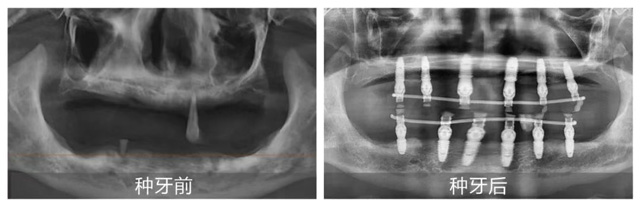

考慮到熊叔叔年齡較大且患有高血壓,全口種植風險大、術后反應強,張潔為其制定半口種植方案。手術在家人陪伴下順利結束,熊叔叔當天就戴上臨時牙冠,恢復基礎飲食功能。他激動地道,“這次終于種上了,原來種牙這么舒適,我根本不用操心,醫護人員領著我檢查,醫生做手術我都沒什么感覺。想到晚上就能吃東西,我太激動了。”

新橋口腔種植修復中心憑借每年成功完成數萬例種植修復案例的技術實力,位居業界前列。中心采用全球各類頂級種植系統,以微創種植、數字化種植、舒適化種植、半全口即刻負重種植為特色,全面開展各類種植修復治療。按照三甲口腔醫院標準,中心建立了口腔種植修復治療區,并配備頂級全進口的口腔CT、全景機等設備,提供尖端數字化影像分析,為種植修復治療提供了完善的硬件保障。未來,新橋口腔將繼續秉持求真務實的態度,持續服務廣大市民,幫助更多缺牙市民收獲好口福!